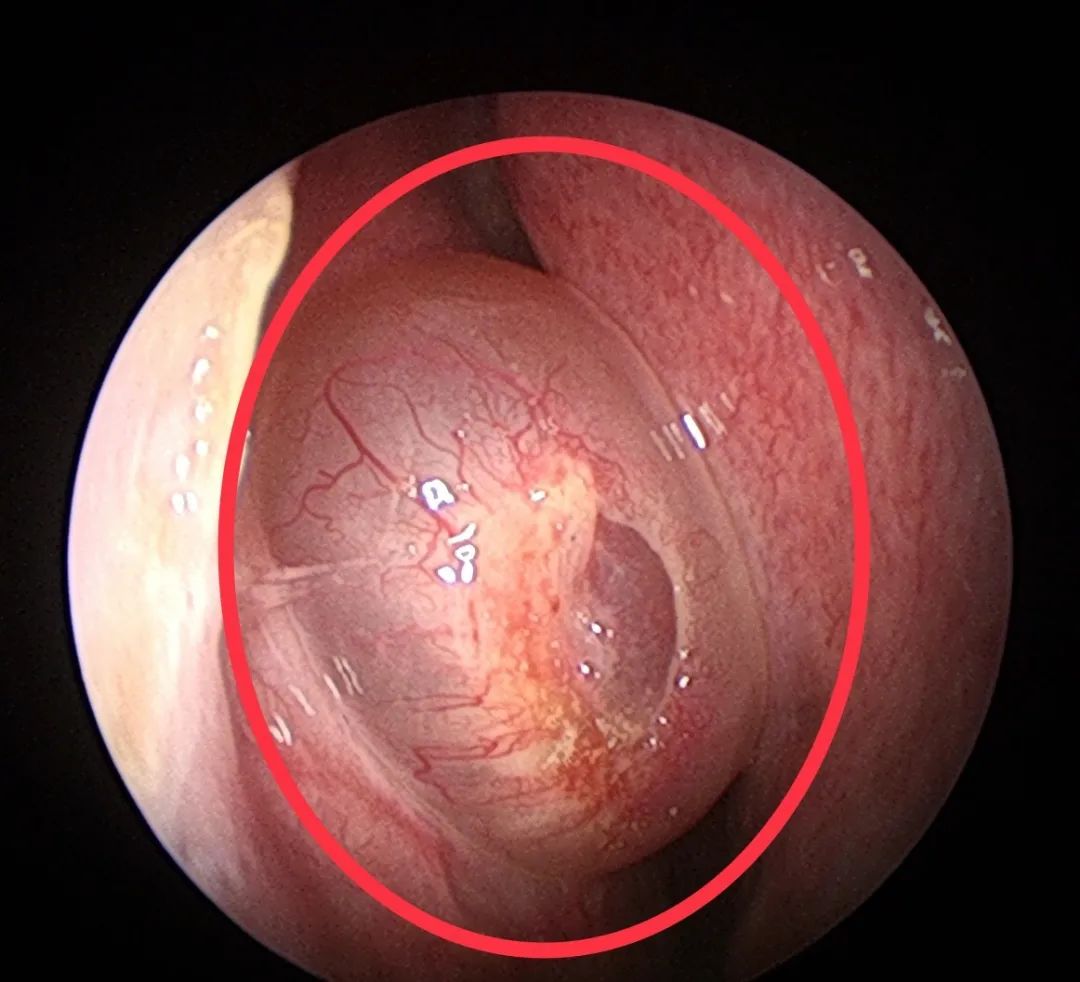

既然这多人都那么怕鼻息肉,那么真正的鼻息肉是啥样子的呢?

下面,我们来看看真正鼻息肉的面目:

其实,鼻息肉之所以让人们觉得那么恐怖,是因为它难以治根,经常复发。近年来,随着鼻内镜微创手术的开展,手术的效果还是不错的。